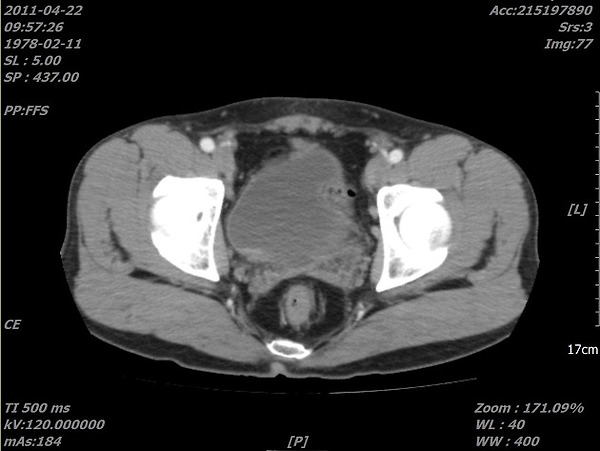

위사진은 암으로 추측되는부분이라도 개인병원 의사가 찾아주신 자료 중 하나입니다.

이게 맞을까요? 첫번째  2011년, 그다음 2015년 세번째도 2011년 그다음 2016년입니다. ....

CT 사진은 음양차이가 굉장히 중요하며 핸드폰으로 찍으신 사진으로는 판단하기가 힘드네요. 마지막 사진방광의 사진상왼쪽에 주변보다 하얗게 보이는 것이 암 소견입니다.

올려주신 영상은 PELVIS 쪽의 조영증강(ENHANCED) CT 검사네요.

첫째, 셋째 사진이 2011(초진검사) 하신 영상이고,

둘째 ,넷째 사진이 15,16년 사진이시죠.

사진이 명확치 않아 확인지 조금 어렵지만

사진상에 보이는 것은 네번째 마지막 사진에만 확실한 종양의심부분이 관찰이 되고 있습니다.

추가질문  「 좀 더 선명한 사진인데....다시한번 봐주시겠습니까..... 」 에 대한 답변입니다.

아. 정확히 보이시네요.

첫번째 사진 2011년 4월22일 ENHANCE CT 영상에서도

동그라미 쳐진 부분(화살표) 부분이 조영증강된 것이 확인이 됩니다.

나머지도 보시기 쉽게 동그라미 표시를 해드렸습니다.